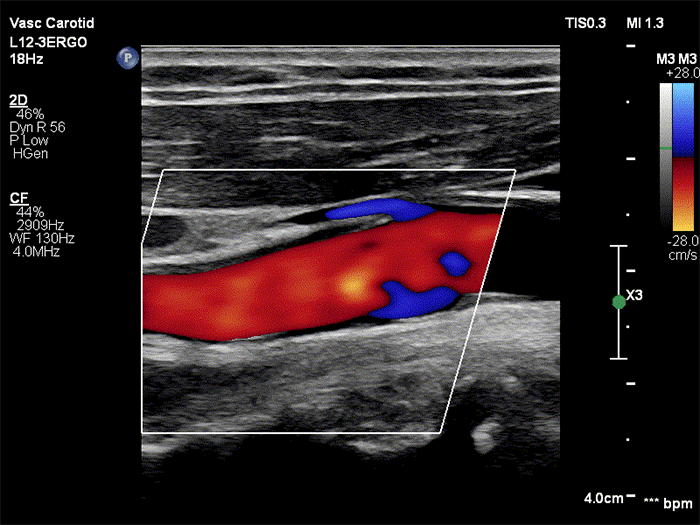

The Philips L12-3ERGO transducer is designed to increase comfort while scanning, specifically for longer periods of use. It includes a new ergonomic form factor and is lighter than the L12-3. The changes made to the transducer include, increased texture on the handle, more pronounced ledge, flatter housing at the nose and ruler lines at the top. Learn more about the L12-3ERGO broadband linear array transducer in the specification table below.